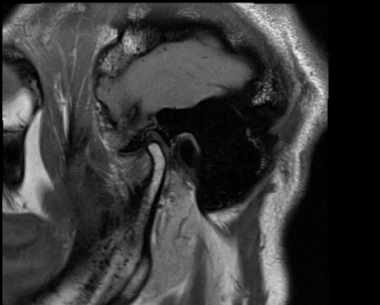

診断、治療計画の中ではMRI画像から軟骨が前方にずれているのが唯一確認出来ます。

私はこのことから顎関節のMRI撮影を行い患者さんの顎関節が正しい位置にあるかどうか?という確認を毎回しております。MRIを確認すると、顎関節の中の軟骨(関節円板)がずれている方に、このような症状が多いと思われます。